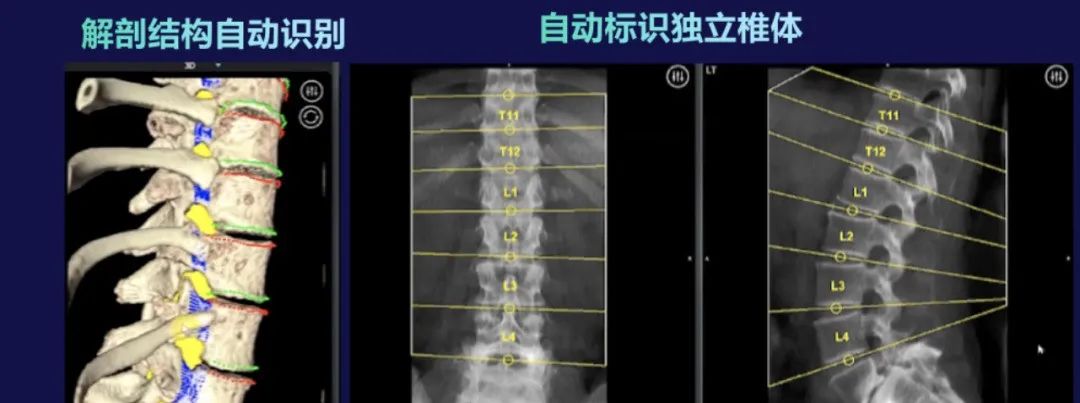

术前计划使用患者的CT数据,凭借Mazor X 的解剖洞察引擎,识别关键解剖结构,通过全局术前规划软件结合人工智能,辅助医生进行多种手术规划,包括螺钉、皮肤切口、通道、融合器规划,脊柱参数测算,畸形分型,截骨矫形模拟等,为患者制定进行个性化、定制化的全局手术规划。

采用单椎体的跨模态配准方式,比通过术中三维扫描配准的传统智能设备更高效,大幅减少辐射剂量并避免术中制定手术计划而增加的额外时间。